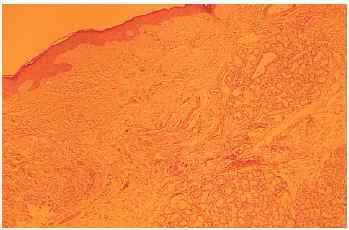

Se realizó una biopsia que mostró un gran número de glándulas salivales de aspecto normal, pero de gran tamaño, que se localizaban cerca del epitelio. Existía un escaso infiltrado inflamatorio constituido casi exclusivamente por células plasmáticas. Además, los ductos glandulares estaban marcadamente dilatados (fig. 2).

Fig. 2.--Se aprecian glándulas salivales hiperplásicas cerca del epitelio, con conductos marcadamente dilatados, con leve infiltrado inflamatorio.